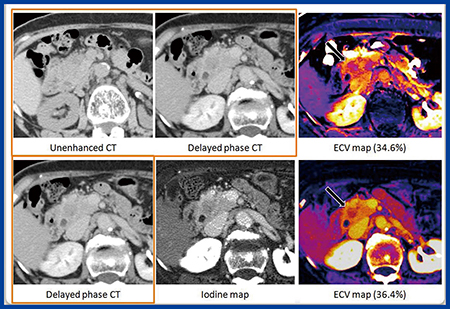

症例3(78歳,男性,浸潤性膵管がん)における通常のサブトラクション法(図5上段)のECV値は34.6%,DECT(図5下段)のヨード密度画像を用いたECV値は36.4%と,ほぼ誤差範囲内の値を示した。ただし,サブトラクション法では,膵頭部の膵管付近に消化管の動きによるミスレジストレーションが見られるが,DECTでは造影平衡相のヨード密度画像のみからのECVマップが得られるため,ミスレジストレーションのない非常に明瞭なECVマップが得られる。

図5 症例3:78歳,男性,浸潤性膵管がん